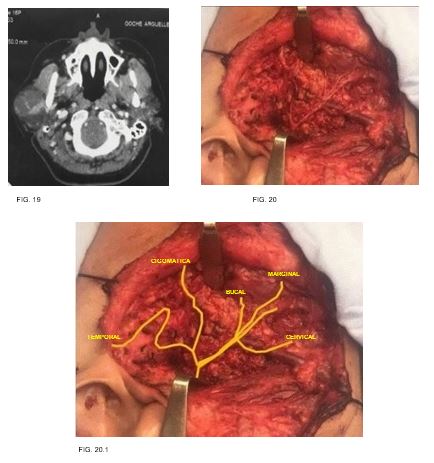

Caso 10: femenino de 45 años de edad, sin antecedentes clínicos de importancia, con tumor parotídeo derecho de 8cm en su eje mayor, resultando en un adenoma pleomorfo. (FIG. 19-20)

Las ramas temporales del nervio facial se encuentran anteroinferior a la arteria superficial temporal, por lo que resulta en un punto de referencia importante para preservar la rama temporal. La rama cigomática transcurrió en todos los casos debajo y paralelo al arco cigomático hasta llegar a la parte inferior del músculo orbicular. La rama bucal corre paralela al conducto parotídeo hacia el músculo buccinador. El origen de la rama bucal ha sido reportada como la más variable de las ramas faciales terminales, por lo tanto, se ha utilizado por algunos autores para clasificar el nervio facial en diferentes patrones de ramificación (Katz y Catalano, 1987;

kwak et al., 2004). 3 Dentro de nuestra descripción encontramos

su origen con mayor frecuencia en el tronco temporofacial (n=5, 50%), en otros tres nervios surgió del tronco cervicofacial (30%) y en una minoría presentó un origen como una raíz doble de ambas divisiones que se unen para formar una sola rama bucal (n=2, 20%). la rama marginal pasa sobre la arteria facial cuando cruza el límite inferior de la mandíbula, en los diez casos se encontró una rama única. En nuestros pacientes, como se menciona en la literatura, se tomaron en cuenta las principales referencias anatómicas como lo son la apófisis vaginal del cartílago tragal, la cual presento distancia promedio de 8.2mm, encontrando un caso en el que este se encontraba a tan solo 6mm del pointer y otros mas en los que la distancia era del doble de esta última mencionada, por lo que esta variabilidad obliga a tomar en cuenta otras referencias importantes en la ubicación del nervio, además de las clásicas, como lo es la apófisis estiloides así como la punta de la mastoides, las cuales invariablemente permiten localizar de forma confiable y segura la salida del NERVIO FACIAL A SU SALIDA DEL agujero estilomastoideo.